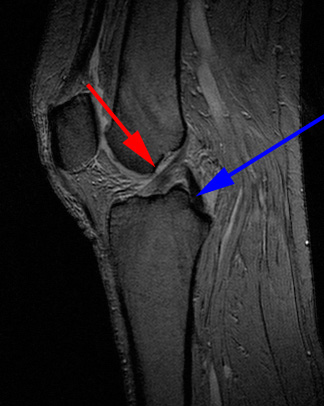

Knæ, Normal (Korsbånd), MR

MR-skanning af knæet der viser normale korsbånd (forreste (rød pil) og bagerste (blå pil)).